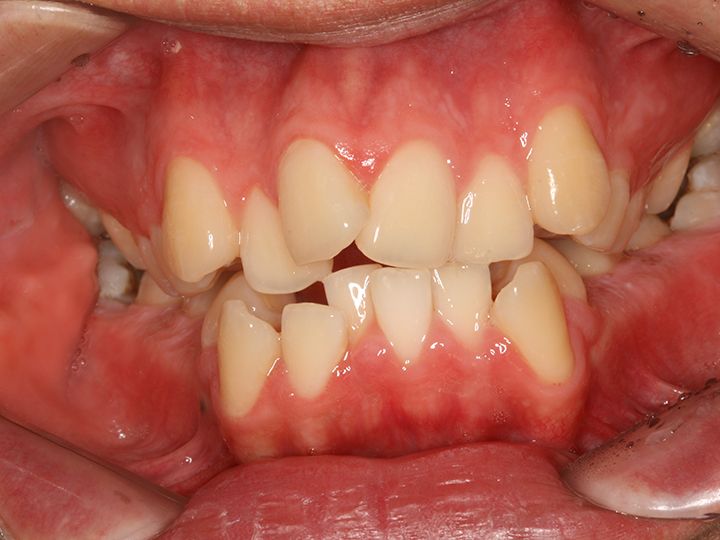

「ライムナム歯科病院」はラミネートやセラミックを使った審美治療、美白治療、インプラント、歯列矯正など、あらゆる歯の悩みに応える歯科病院です。2004年の開業以来、常に新しい技術と診療機器を取り入れ、韓国内外の患者の信頼を集めてきました。特に忙しい現代人の悩みである時間短縮治療メニューが充実。来院当日にできるだけ解決できるようなシステムを構築しています。独自の歯科技工所を持っているのもその理由のひとつ。また20年にわたるノウハウの蓄積を生かし、患者の負担を減らせるように痛みを減らす施術にも力を入れています。